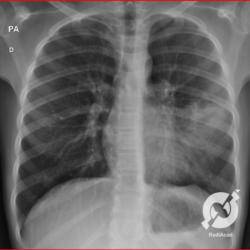

Os agentes etiológicos infecciosos são variados (bactérias, vírus, fungos, parasitas…), mas o que ocorre nos pulmões durante uma infecção por qualquer tipo de agente é a substituição do ar alveolar por secreção (pus, muco, eventualmente sangue ou necrose…) e com isso a manifestação radiográfica vai ser a mesma já que todas estas secreções apresentam a mesma densidade radiográfica: partes moles.

E o nome dado a esta alteração radiográfica que corresponde à substituição do ar alveolar por líquido é a consolidação alveolar.

Uma consolidação alveolar é, por definição, uma opacidade (imagem densa, branquinha) homogênea ou às vezes heterogênea (pela presença de calcificações ou cavidades), de limites mal definidos, exceto quando toca a pleura da parede ou das cissuras pulmonares. É um termo usado tanto em radiografia, como em tomografia computadorizada. Na tomografia, um outro termo é usado: vidro fosco, que é uma opacidade (branquinha mas não tanto como a consolidação), que borra o pulmão mas deixa ver os vasos de permeio (igual bigode de adolescente: dá pra ver todo o fundo).

Nós vamos mostrar aqui um pequeno apanhado de pneumonias de variados agentes, em diversos segmentos e lobos pulmonares, com extensões variadas. O objetivo é identificar o padrão radiológico de consolidação alveolar e não determinar o agente infeccioso, isso vai ser assunto para mais adiante. Aliás já antecipo que é fundamental saber localizar a lesão, porque alguns destes bichos gostam de determinados segmentos, alguns tumores também têm as suas preferências, então localização é fundamental. Se localização não fosse importante, um apartamento na beira do mar sairia o mesmo preço de um apartamento de frente pra BR-101, concordam?

Seguem alguns dos nossos casos de pneumonia para vocês treinarem os olhos e não se apavorarem nos plantões.